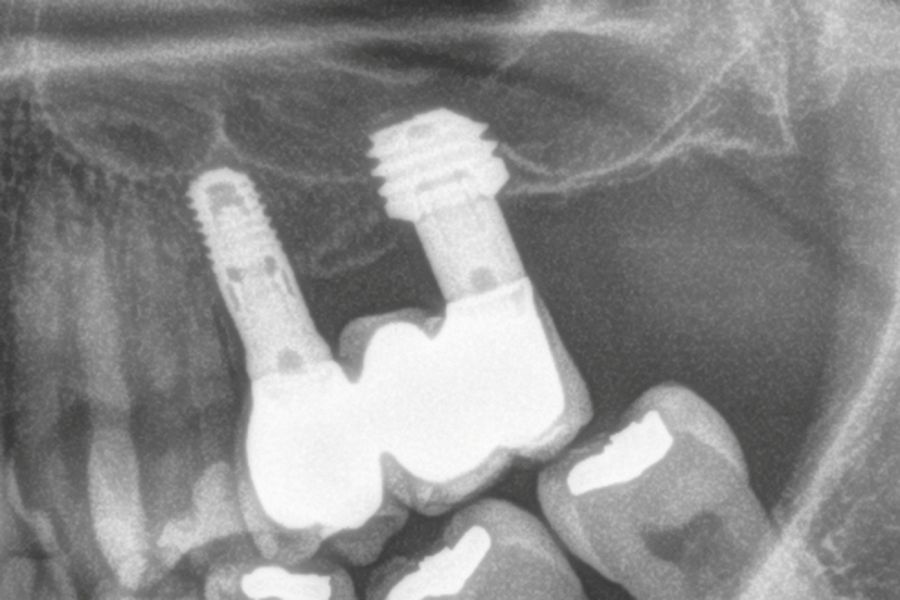

El acceso final a la cortical sinusal se efectuó con una fresa específicamente diseñada para esta técnica (fresa de corte frontal), la cual permite la eliminación controlada del suelo del seno maxilar sin comprometer la integridad de la membrana de Schneider10. Una vez expuesta la membrana a través de la perforación en la cresta ósea, se realizó su elevación de manera controlada, colocándose el injerto consistente en hueso autólogo obtenido del fresado de otras localizaciones en las que se colocan implantes en el mismo acto quirúrgico embebido en PRGF-Endoret. Por último, la colocación del implante se llevó a cabo con un motor quirúrgico calibrado a 25 Ncm y 25 rpm, mientras que la inserción final se realizó manualmente mediante una llave dinamométrica para asegurar una fijación óptima (Figura 1).

Entre cuatro y cinco meses meses después se realiza la carga del implante, en una primera fase con una prótesis provisional de carga progresiva, siempre mediante transepiteliales y, posteriormente la prótesis definitiva entre 1 y 2 meses tras la carga inicial.

El diámetro de los implantes osciló entre los 3,75 mm y los 6 mm, siendo el más frecuente 4,25 mm y 4,75 mm con un 27,8% para cada grupo. Todos los implantes colocados fueron de 4,5 mm de longitud. Los diámetros y longitudes de los implantes incluidos en el estudio en función de la posición se muestran en la Figura 4.

En las Figuras 7- 13 se muestra uno de los casos incluidos en el estudio.